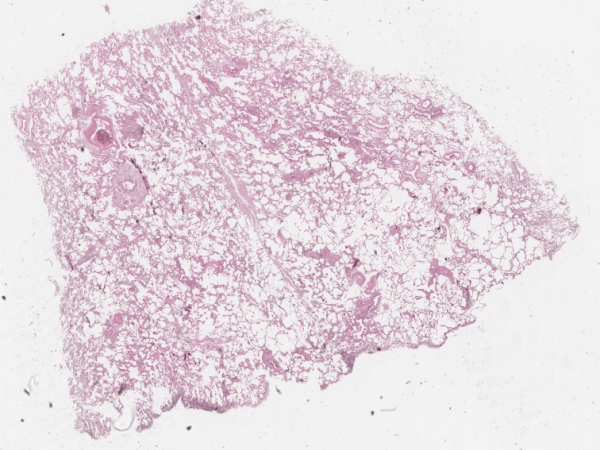

Бронхиектазии

Виждам бял дроб(алвеоли, бронхи, хиалинен хрущял и кръвоносни съдове ). Бронхите са дилатирани и разширени в сравнение с кръвоносен съд в съседство. В лумена на част от бронхите възпалителен инфилтрат ( ексудат ). Въпроси? Видове бронхиектазии? – от учебника. Усложнение на бронхиектазиите? Бронхиектатичната болест – секрета се задържа ( възпаление ) и може да доведе…